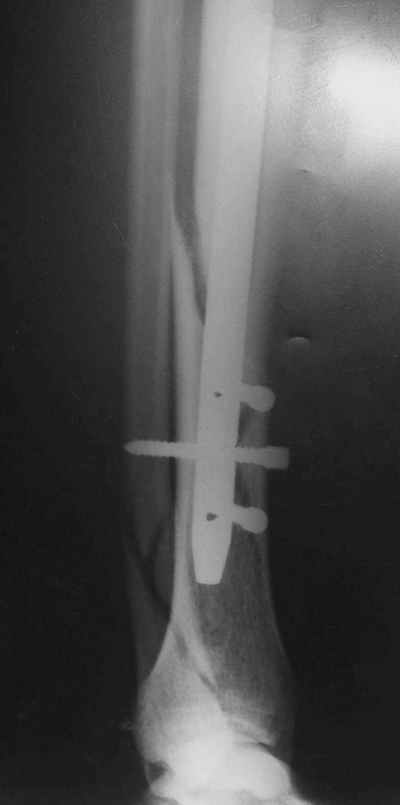

В 2002 г. была у нас больная с ложным суставом бедра и остеомиелитом (как оказалось), после удаления пластины. Гвоздь с блокированием.

Потекло через месяц - открылось 2 свища по старому рубцу от давно удаленной пластины. На фоне гноя раза три завинчивал обратно винты, которые вылезали латерально, прямо через свищ. Потом таки провел дополнительно винты мимо гвоздя, и убрал вверху статический винт. Острый гнойный процесс стих, свищи мыла она дома дважды в день водным хлоргексидином, ходила с возрастающей нагрузкой, а к 10 мес. и свищи закрылись, и срослось. Итоговые снимки от 18 апреля 2003 г. прилагаю.

Выполненный остосинтез нестабилен. Штифт надо заменить по "размеру" на солидный, дистльно три запирающих винта. Успехов!

Перелом спиральный, то есть низкоэнергетический, так что со сращением дело обстоит уже неплохо, лишь бы "костоеда" не развилась. Отломки выглядят уже стабилизированными костной мозолью, так что довводить винты, наверно, уже незачем. Разве что при клинической оценке подвижность еще есть - тогда можно для стабилизации наложить простейший аппарат, не опасаясь контакта его элементов с гвоздем, поскольку места в дистальном метафизе оставлено более чем достаточно.